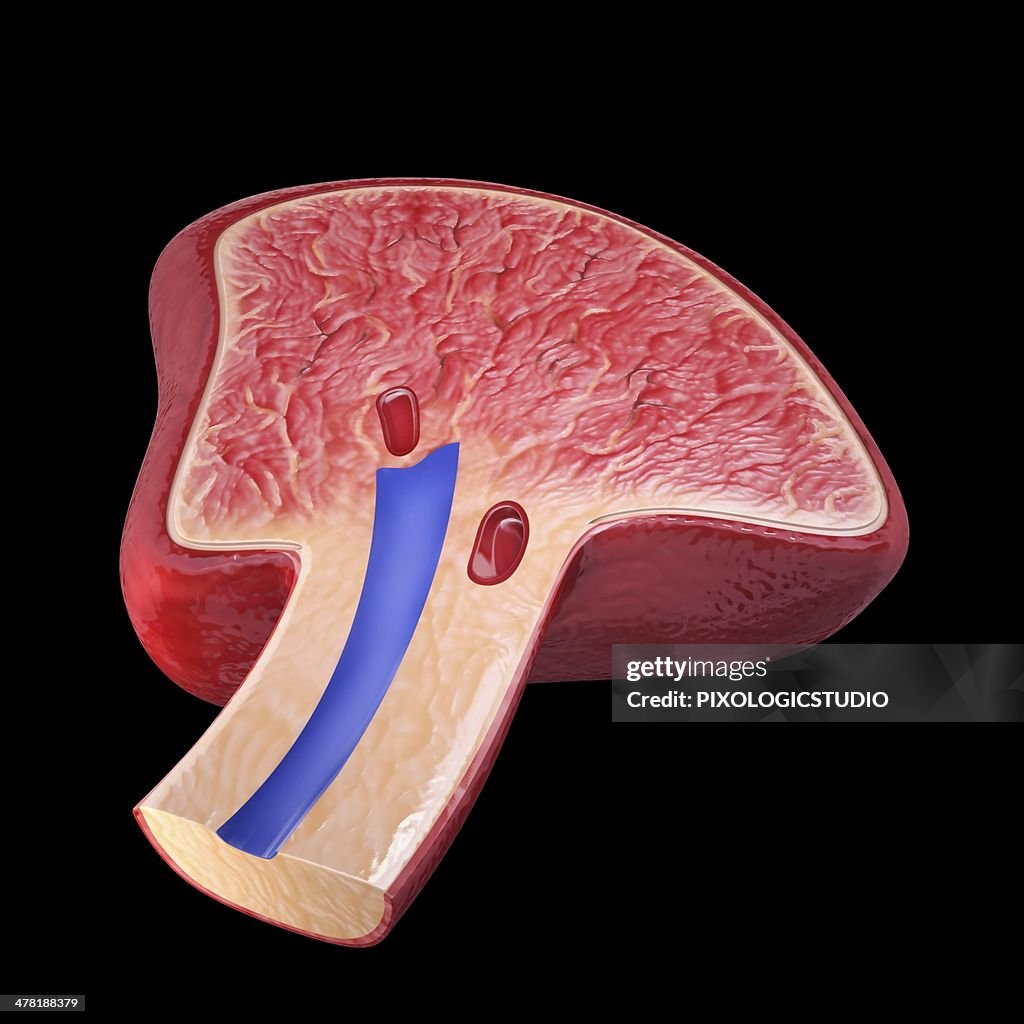

Human spleen, artwork - Illustrations

Human spleen, cut-away computer artwork.

- Anatomie,

- Artère,

- Artère splénique,

- Coupe transversale,

- Illustration biomédicale,

- Rate,

- Système immunitaire,

- Vaisseau sanguin,

- Vue en coupe,